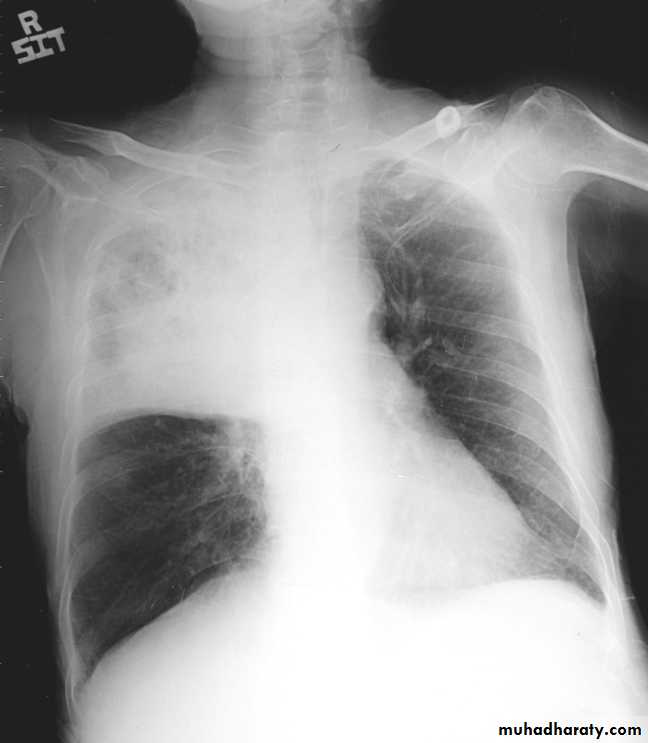

Total collapse total consolidation

Total collapse

48.opasified hemi thorax

49.total collapse